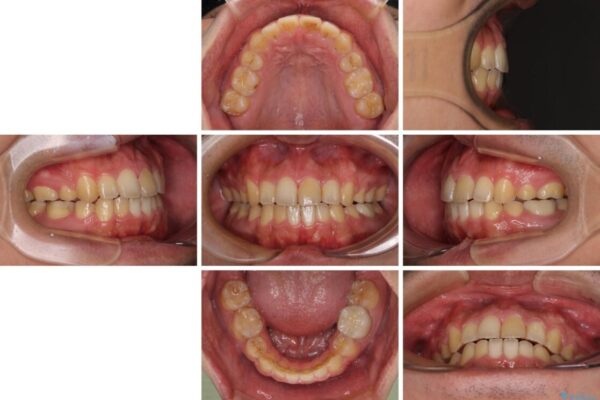

高校時代に行った抜歯矯正が後戻りをしたとのことで来院された患者様です。

再矯正であることから、目立ちにくい装置を希望されたため、インビザラインにて矯正治療を行うこととしました。

下顎骨が左側に変位しているため、正中が合わないことは予想できましたが、歯列が整った後も咬み合わせが安定せず、咬み合わせを落ち着かせるために1年以上の期間を要しました。

噛みにくさの改善に時間がかかってしまうことがインビザラインの欠点の1つといえます。

治療前

• 後戻りでデコボコの前歯 インビザライン矯正治療 治療前画像